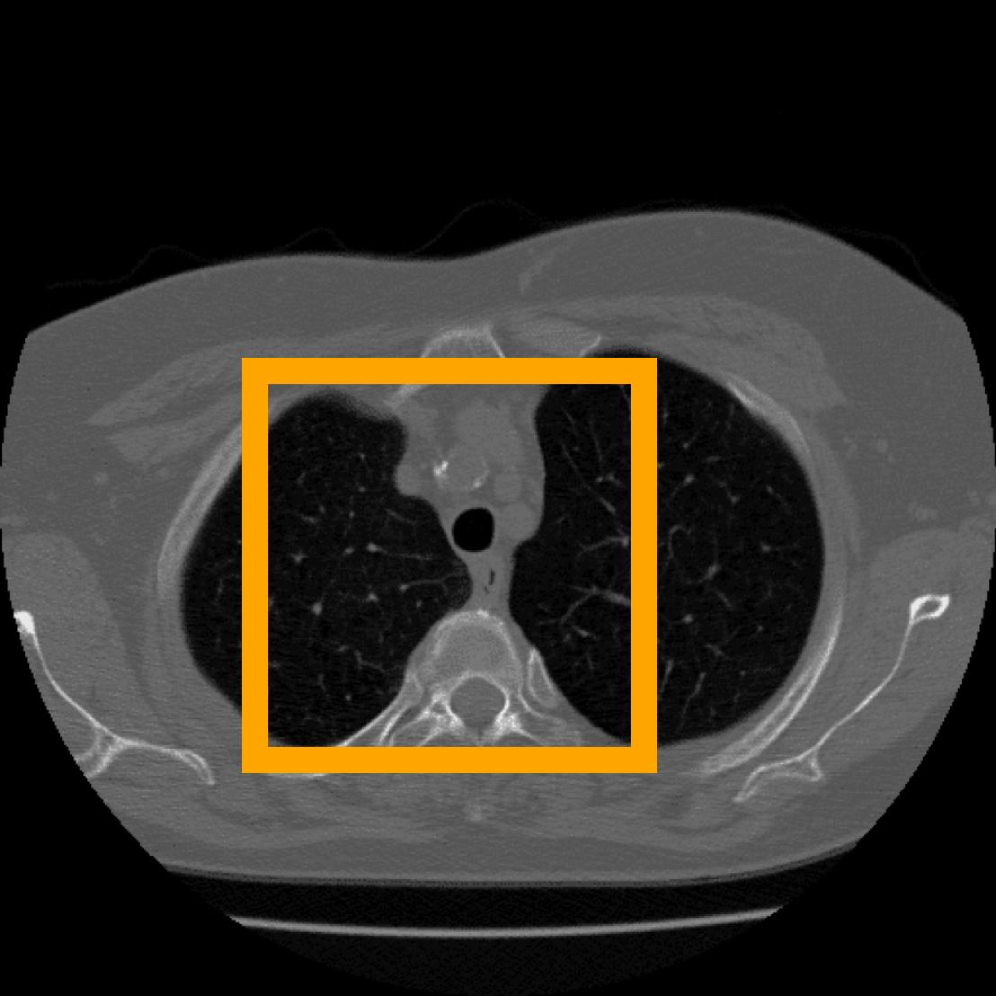

In addition, we use the CT Heart Segmentation dataset [NikhilTomar], which contains a series of 2D computed tomography (CT) heart scans with the resolution of 512 ×\times 512. This dataset provides clear anatomical structures of the human heart, and is widely used in medical image segmentation and compression tasks. Its inherent slice-based nature naturally aligns with our patch-based INR compression strategy, allowing us to further evaluate the effectiveness of COLI for medical images with rich structural information.

Figure 11: Zoomed-in view of the highlighted region in Figure 10.

Figure 12: The visual comparison of different compression methods on another CT Heart Segmentation image.

Figure 13: Zoomed-in view of the highlighted region in Figure 12.

IV-B3 Visual Comparison

Figures 7 and 8 present representative examples from the CIL dataset and their zoomed-in regions, respectively. For the CT Heart Segmentation dataset, Figures 10 and 12 illustrate typical reconstruction results, while Figures 11 and 13 further enlarge local regions to compare structural details. Across both datasets, COLI preserves fine structures and global continuity well even at relatively low bpp. Specifically, on the CIL dataset, COLI attains the lowest bitrate among INR-based methods while still maintaining clear texture details. On the CT Heart dataset, COLI also operates at a low bpp within the INR family and delivers superior visual quality with improved detail fidelity and smoother structural presentation. The zoomed-in regions show fewer blocking artifacts and smoother transitions, making COLI especially suitable for large images and medical images. These visual results validate that INR-based compression can achieve efficient storage with reliable perceptual consistency, offering practical advantages for real-world large-scale image processing.